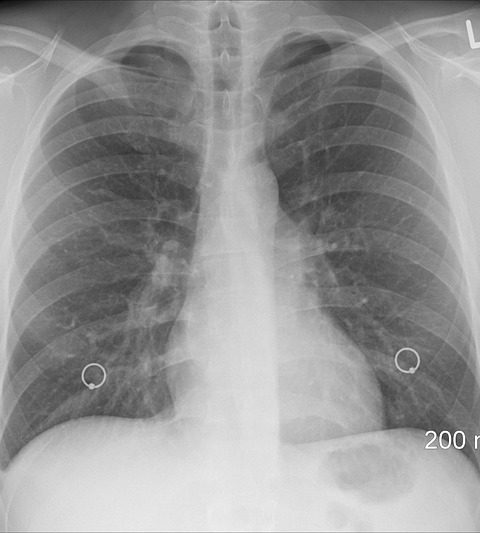

I polmoni umani sono divisi in cinque lobi: tre nel polmone destro e due nel sinistro. Il polmone destro comprende il lobo superiore, il lobo medio e il lobo inferiore. Il polmone sinistro, invece, è composto dal lobo superiore e dal lobo inferiore. Questa divisione permette ai polmoni di funzionare in maniera più efficiente, consentendo una distribuzione equilibrata dell’aria durante la respirazione.

Ogni lobo è ulteriormente suddiviso in segmenti bronchiali e alveoli, che sono le unità funzionali del polmone dove avviene lo scambio gassoso. Gli alveoli, in particolare, sono piccole sacche d’aria che consentono all’ossigeno di entrare nel sangue e all’anidride carbonica di essere espulsa. Questa struttura complessa e ben organizzata è fondamentale per un’efficace funzione respiratoria.